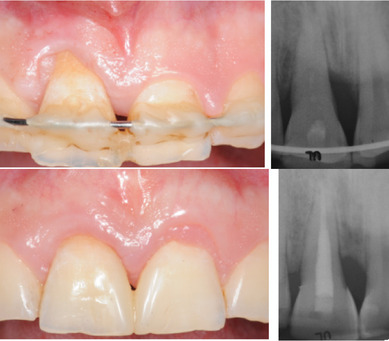

Une nouvelle procédure, combinant une technique de préservation papillaire avec greffe de tissu conjonctif et lambeau déplacé coronairement, sera présentée. La greffe de tissu conjonctif joue le rôle de paroi vestibulaire du défaut intra-osseux, traité par apport d’amélogénines, augmentant ainsi la stabilité du caillot

sanguin pour favoriser la régénération parodontale et améliorer le résultat esthétique.

Les facteurs décisionnels dans le choix de la thérapeutique (régénération ou extraction) liés aux tissus mous seront détaillés. Les objectifs pédagogiques de cette formation seront de répondre aux questions suivantes :